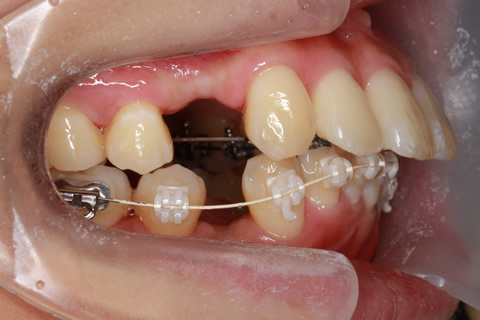

ハーフリンガル矯正3:上の歯のみ舌側矯正で治療(矯正期間24ヶ月)

治療中(開始半年後)

- 年齢・性別

- 25歳女性

- 治療期間

- 2年0ヶ月

- 抜歯

- 上下4番抜歯

- 治療費

- 110万円

- 治療内容

- 施術の副作用(リスク)

- 表側矯正と比較して、力学的な操作性が複雑なため、ボーイングエフェクトを起こしやすい。